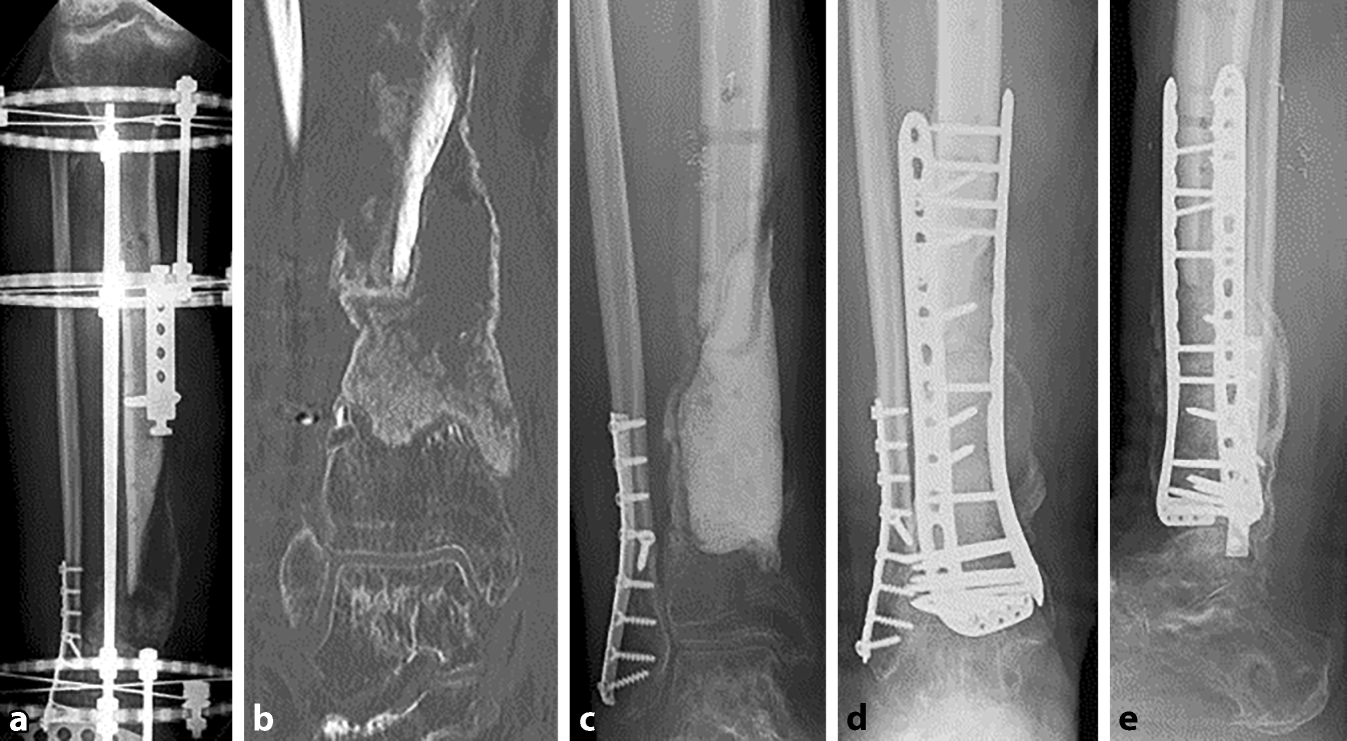

Abb. 2

a Segmentdefekt der distalen Tibia mit Verlust des oberen Sprunggelenkes, Spacer und temporäre Stabilisierung mit Kirschner-Drähten, b MT mit 2 Femurköpfen und mittels RIA gewonnener Spongiosa, retrograde Marknagelarthrodese des Sprunggelenkes, c CT nach 4 Monaten mit vollständiger Konsolidierung; d 9 cm langer Segmentdefekt am Femurschaft, temporäre Osteosynthese durch Marknagel, e MT durch 2 Femurköpfe und RIA-Spongiosa, vollständige Konsolidierung nach 4,5 Monaten, hochstabile Osteosynthese durch Nagel und Plattenosteosynthese

Absolute Stabilität von Osteosynthese und Masquelet-Plastik sind die Voraussetzungen einer erfolgreichen Therapie. Liegen Defekte im Isthmusbereich langer Röhrenknochen vor, kann die Osteosynthese mit einem ausreichend starken Nagel genügen. Liegt keine ausreichende Stabilität vor, sollten zusätzlich winkelstabile Platten verwendet werden (Abb. 2e, 3d und 4b). Im Gelenkbereich werden typischerweise winkelstabile Doppelplattenosteosynthesen angewandt (Abb. 1d, e).